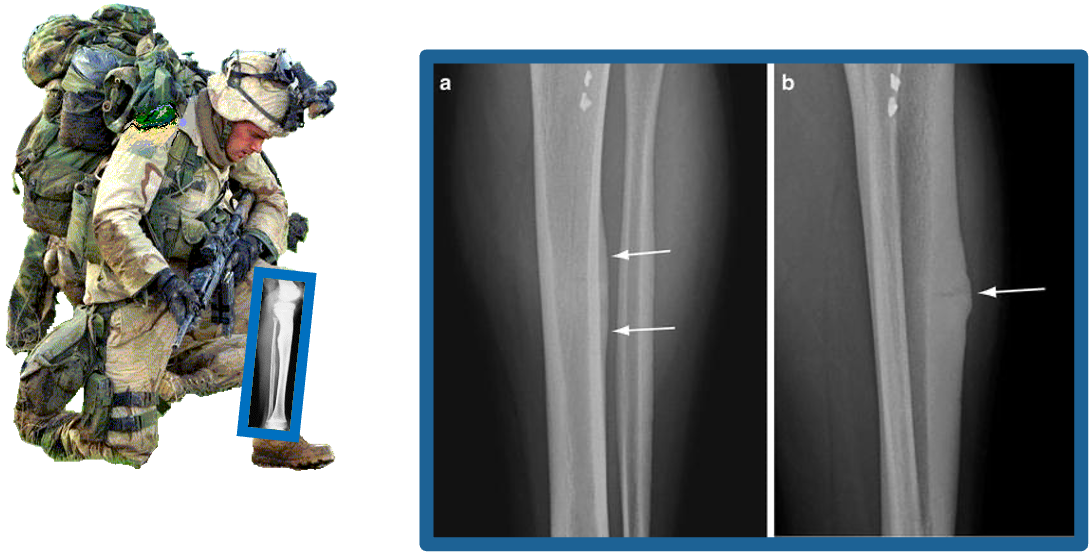

Stress fractures in military recruits

Investigating why some recruits are more vulnerable to stress fractures during basic training

StressFx